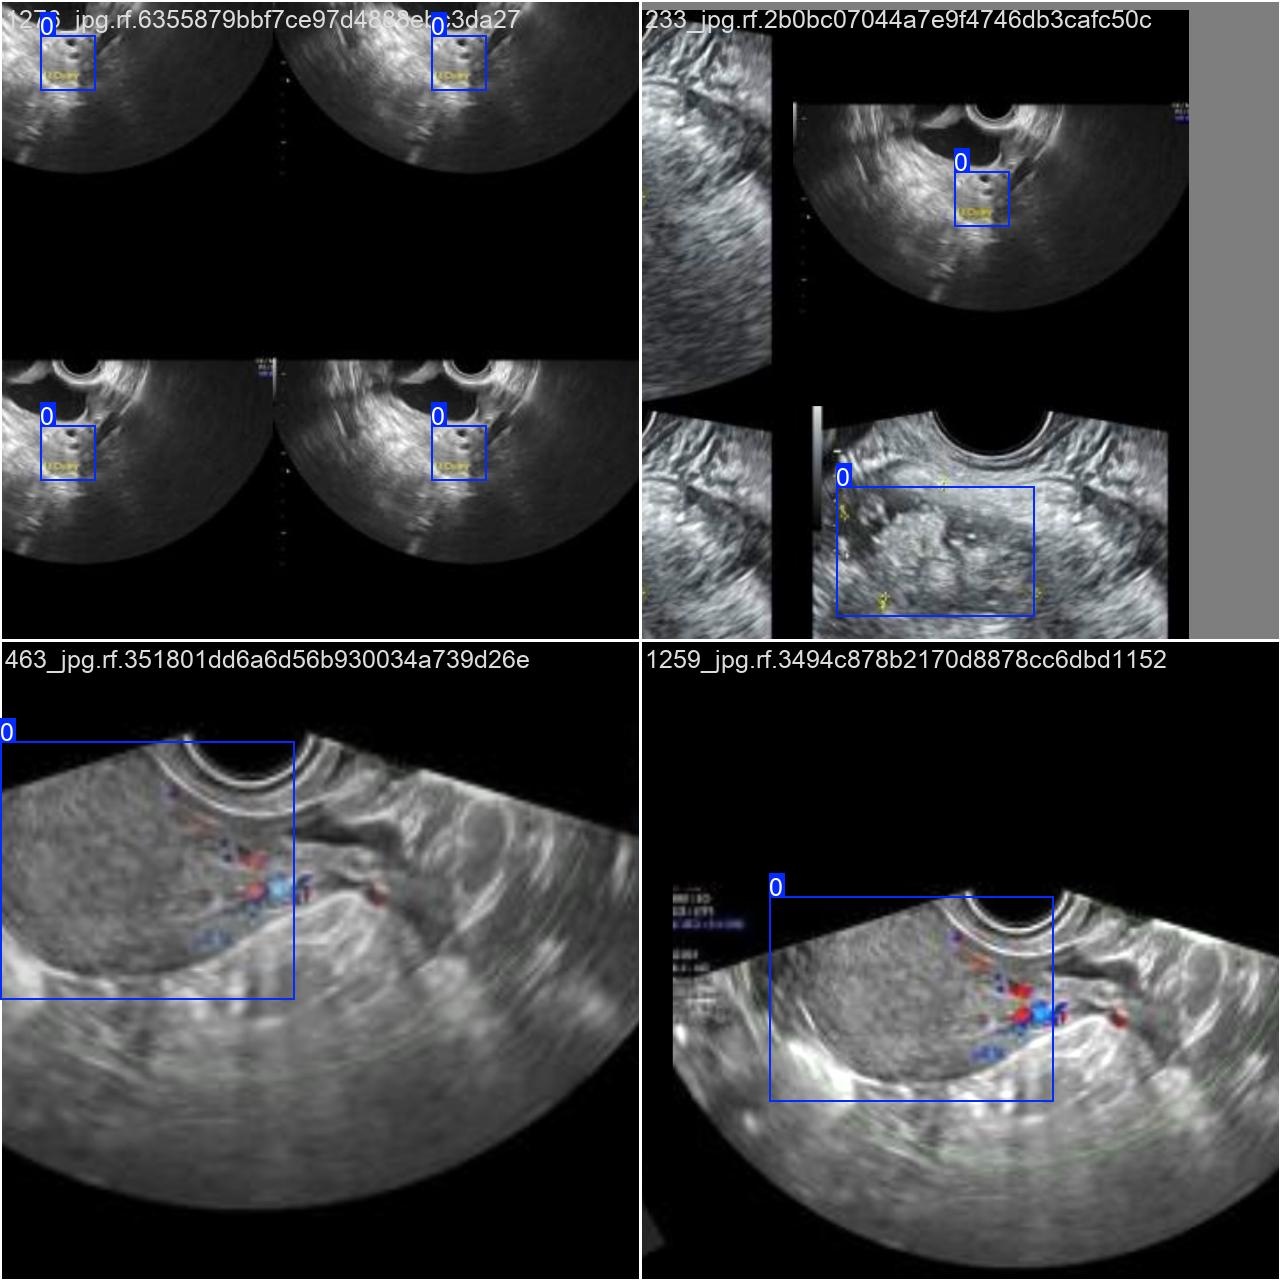

部分数据集图像如下图所示:

部分标注如下图所示: